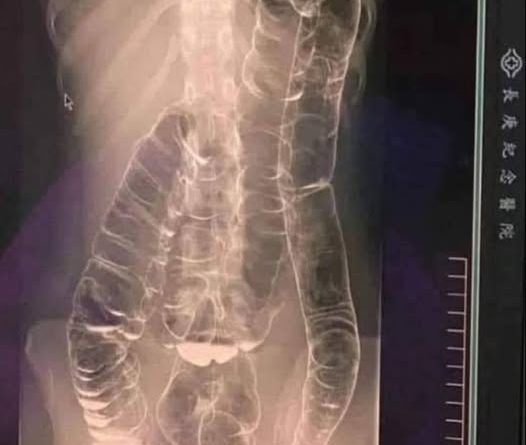

Це саме те, що сталося з молодою жінкою, чия застійна товста кишка небезпечно збільшилася.

Це крайній випадок, але він чудово ілюструє несподівану небезпеку тривалого запору. Отже, як ми можемо запобігти різкому розвитку цієї хвороби травлення?